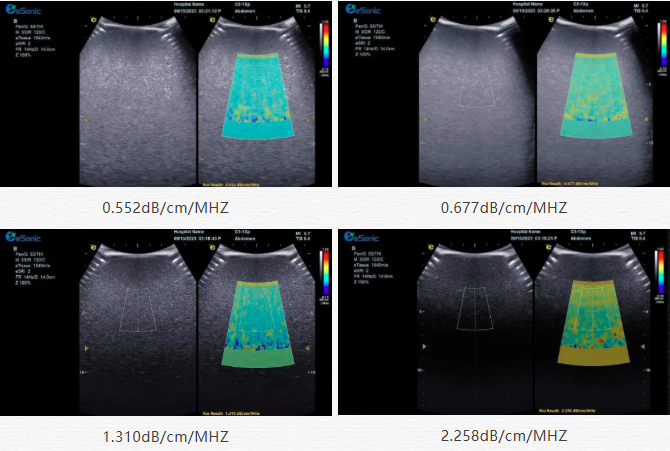

该技术基于声波在介质传播时的衰减,衰减由声吸收、反射、散射及波束扩散所致,声衰减系数(α,单位 dB/cm?MHz,与超声频率和传播距离成正比)可通过测定同频超声波在组织中的衰减程度,借回波信号分析预测声衰减系数或衰减率来评估组织特性。

目前市面常用瞬时弹性成像或仿体参照法,存在适用性、准确性差及无衰减图局限。利来国国际网站则采用准确度更高的 ALA 幅度损失衰减法,超声波深度传播时回波幅度渐降,其对数与深度有良好线性关系,声衰减量与传播衰减系数成函数关系,调节取样框大小位置可实时得样框内组织衰减系数,用于定量评估病变程度。

声衰减定量成像技术的应用范围非常广泛,包括肝脏疾病、乳腺肿瘤鉴别、肾脏病变以及肌肉骨骼系统等多方面的病变。712a8084746869e803a3684e2526ee4.png肝脏疾病诊断在脂肪肝的评估中,脂肪作为一种声衰减介质,超声波在脂肪肝内的传播会产生衰减,肝脏中脂肪组织比例越大,超声衰减就越高。在肝硬化患者的肝脏中,肝脏组织的纤维化和结构改变会导致超声声衰减特性的改变。声衰减成像技术可以帮助医生观察肝脏实质的变化,辅助判断肝硬化的程度,同时对于监测肝硬化治疗过程中的病情变化也有一定的价值。